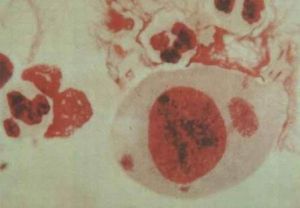

根據許多國家報告,NGU中30%-50%,淋病病人中20%和性活動強但無尿道炎症狀的人中0.5%,以目前常用的培養方法,尿道分泌物可培養出衣原體。女性病人因多數無症狀或僅表現為白帶增多等婦科症狀,難以確定其發病率,有人估計女性病人可能為男性的4倍。衣原體是一種寄附於腺上皮細胞胞漿內的微生物。呈球型,有特殊的生長周期。每個生長周期有兩種發育型。感染型為原體(elementarybody)呈球形,大小介於細菌與病毒之間(300-400mm)。原體可在細胞外生存,有感染性。當其附著在易感細胞表面時,被細胞吞飲,在細胞內原體變成另一種繁殖型。繁殖型即始體(initialbody)始體呈圓形或橢圓形。始體按二分裂方式繁殖,最後始體重新組織成原體,從細胞內釋放出來,再感染其他健康易感細胞。整個生長周期為72h。衣原體分類:1、鸚鵡熱衣原體。2、沙眼衣原體(Chlamydiatrachomatis)沙眼衣原體至少有15個血清型。D-K8種血清型與NGU有關。L1、L2、L33個型與性病性淋巴肉芽腫(第四性病)有關。支原體